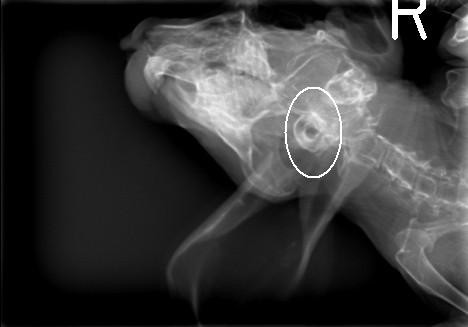

Now for the xrays (Though I probably didn’t need to say that-you could probably guess by looking at them

Thought this one was cool-you can see his teeth look great!!

So do they help indicate anything?

Well their are two main causes but there are other causes like stroke, tumor abscess-so they eliminated that; AND the ‘bulba’ (sp??) are thickened which may be incidental but may be something so they were good to do-I’d like-eventually to do xrays on everyone but at this point only when necessary.

The dark parts in the centre are his ‘bulba’ they are basically round thing at the base of the ear canal. They are thickend which is why they are showing up so much-this could be nothing , why he’s deaf, or someting we need to treat after the tilt is treated. They shold be nice light circels like his eyes (you can sort of see his eye sockets in one of the pics) -I thnk thats what you were asking about.

Actually I have a hard time with xrays-one fo the reasons I wanted them-she spent a long time going over everything with me on them.

Hehe OK the first xray you posted is a top down-so where the R is-is his right hand side, and left is left of the picture.

The second one-that’s a hard one

He’s partially upside down in that one. In the top right you can see his arms. the face is pretty blurry and his ears are dangling bottom left ![]()